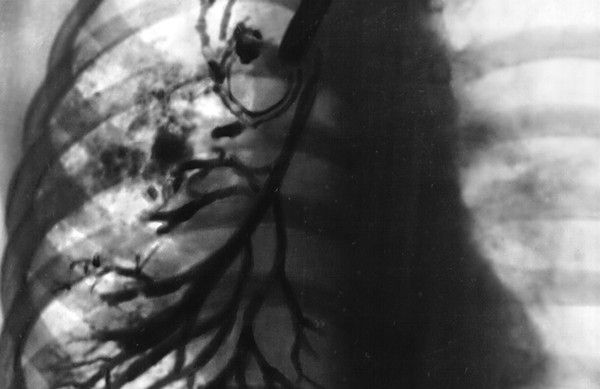

Несмотря на то, что спектр болезней органов дыхания достаточно широк, в центре внимания врачей оказалось одно из самых тяжелых генных заболеваний — муковисцидоз. Напомним, причиной плохой работы дыхательной системы у подобных пациентов является слишком вязкие и густые секреты, выделяемые различными органами. В результате страдает бронхолегочная система, поджелудочная железа, печень, железы кишечника, потовые, слюнные железы и половые. Скапливающаяся вязкая мокрота провоцирует воспалительные процессы в легких, что приводит к возникновению мучительного кашля. У пациентов развиваются повторяющиеся бронхиты и пневмонии, иногда уже с первых месяцев жизни.